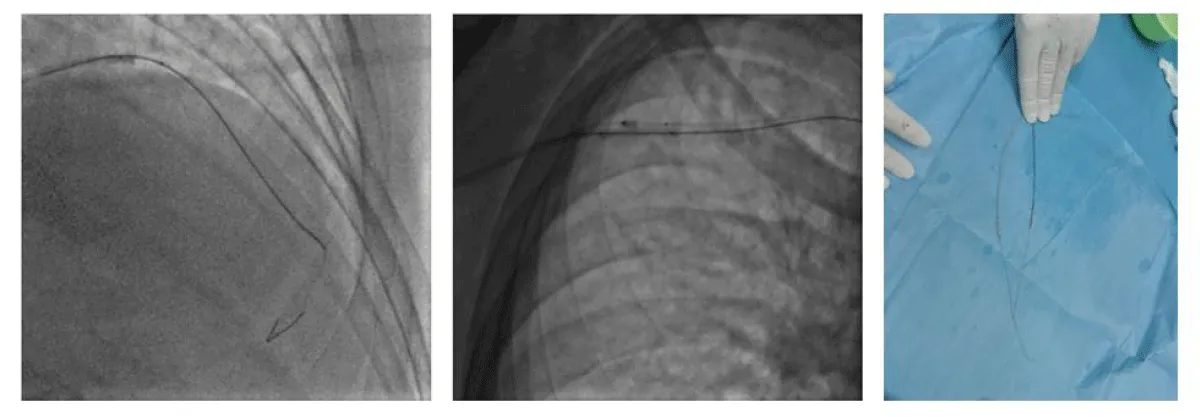

We started the procedure under 5000 UI of Heparin with an Extra Backup (EBU) 3.5 6 F guiding-catheter, we crossed the lesion with a floppy guidewire, however after dilatation with an NC balloon 2.5 × 12 the latter refuses to deflate and remains trapped in the lesion with the appearance of pain and an ST segment-elevation despite several attempts to dilute the product in the inflator and to burst it by overexpansion (Figure 2).

Figure 2: PCI and balloon trapping.

A traction on the balloon resulted in the deep intubation of the guiding-catheter which comes in contact with the trapped balloon and the rupture of the latter’s hypotube, which remains inflated at the site of the lesion partially in contact with the guiding-catheter and mounted on the 0.014 guidewire (Figure 3).

Figure 3: Rupture of the hypotube and guiding catheter deep intubation.

We put the second 0.014 guidewire distally in the LAD and twisted it with the distal part of the first guidewire, then we introduced a second balloon 2.0 × 20 over the second guidewire until the distal part of the guiding-catheter and inflated it between the guiding-catheter and the lesion to trap the stucked balloon between the second balloon and the guiding-catheter and to modify the lesion (to create a Cage and Buddy-balloon) (Figure 4).

Figure 4: Cage and Buddy-balloon./p>

We gradually removed this emergency assembly that allowed us to release and retrieve the trapped balloon (Figure 5). The control injection revealed a thrombotic occlusion of the LAD treated by thrombectomy and anti-GPIIbIIIa followed by a DES 2.75% 28 placement that allows a TIMI III flow in the LAD at the cost of losing the small diagonal artery that we could not recross (Figure 6).

Figure 5: Trapped balloon retrieval.